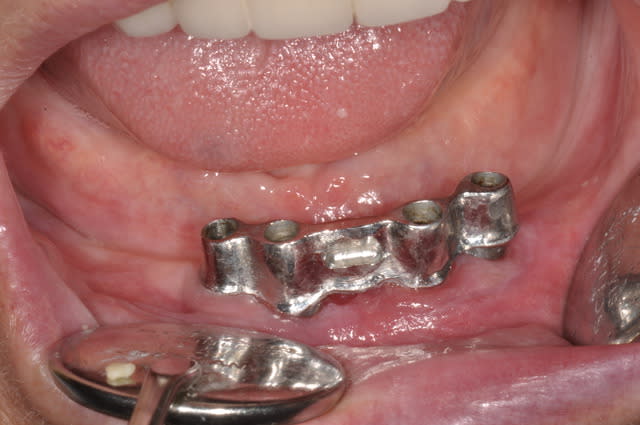

pano 5 et photo 6 ce matin